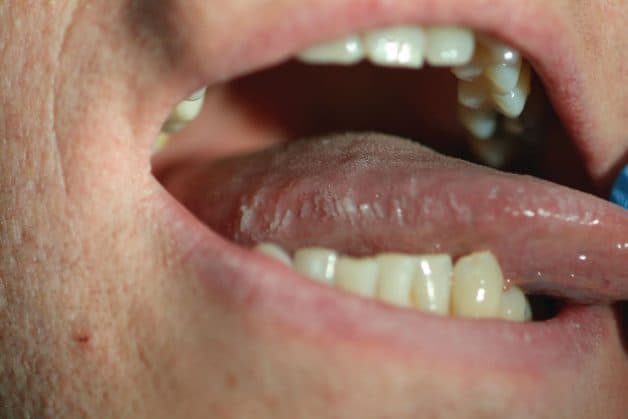

– Với bạch sản dạng lông, triệu chứng thường gặp là lông xuất hiện, có những mảng trắng mờ dạng nếp gấp hoặc đường lằn ở hai bên đầu lưỡi.

Với bạch sản dạng lông, triệu chứng thường gặp là lông xuất hiện, có những mảng trắng mờ dạng nếp gấp hoặc đường lằn ở hai bên đầu lưỡi